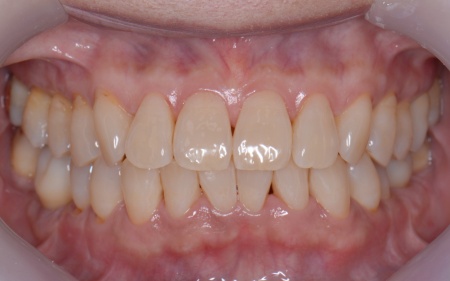

さらに虫歯が再発していた左上奥歯については、虫歯をしっかりと取り除いたうえで被せ物による修復治療を提案しました。 それぞれのメリット・デメリットを丁寧に説明したところ、治療計画に同意いただきました。 まず、歯周基本治療から開始しました。 下左右の第1大臼歯を抜歯し、その部位にインプラントを埋め込む手術を行いました。同時に、インプラントの隣にある下の第2大臼歯に対して歯周組織再生療法を施しています。 また、左上の奥歯は虫歯を取り除いたあと、歯の形を整えて型取りを行い、最終的にジルコニアクラウンを装着しています。 段階的に治療を進め、すべての治療を終了しました。 |

| 治療期間 | 約1年2ヶ月 |

| 費用 | 約1,930,000円 【内訳】 歯周組織再生療法4ヶ所、インプラント2本、角化歯肉移植、ジルコニアクラウン |